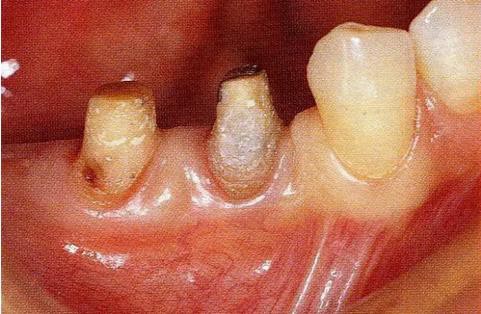

圖18-1(左),2 (右)▲  初診時(shí)口腔內(nèi)照片和X線片,右下4近中有較深的1壁性骨缺損,右下45有根接近。如果在這個(gè)情況下進(jìn)行骨外科處理,需要犧牲較多的右下3遠(yuǎn)中的牙槽骨。也會(huì)造成周?chē)切纬奢^大的臺(tái)階。